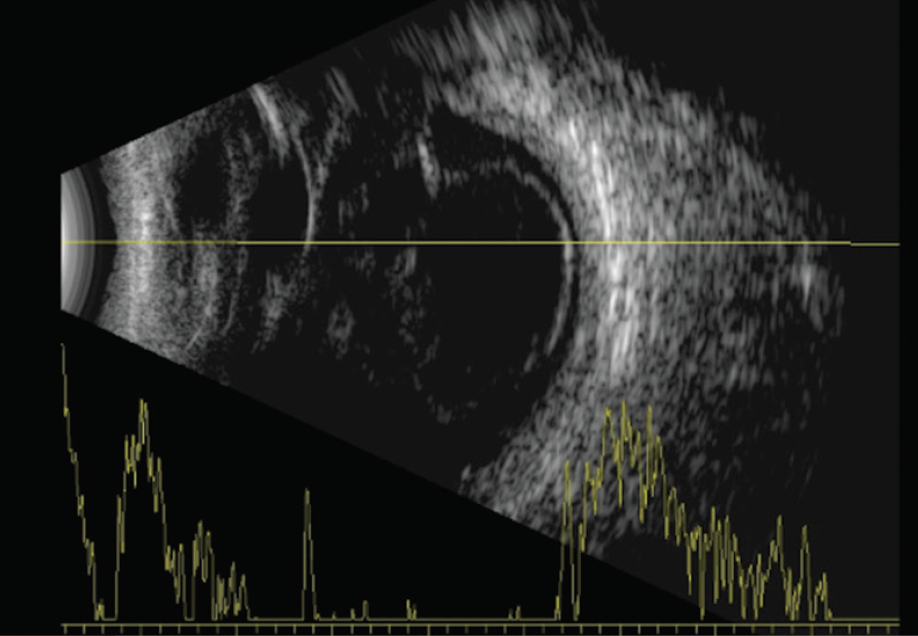

A 76-year-old man experienced blunt trauma to his left eye that resulted in a 50% hyphema, a dislocated cataractous crystalline lens, total retinal detachment with GRT, and massive subretinal and vitreous hemorrhage with PVR (Figure 1). VA in the left eye was light perception.

<p>Figure 1. Ultrasound image shows detached retina, vitreous hemorrhage, and thickened choroid.</p>

Figure 1. Ultrasound image shows detached retina, vitreous hemorrhage, and thickened choroid.